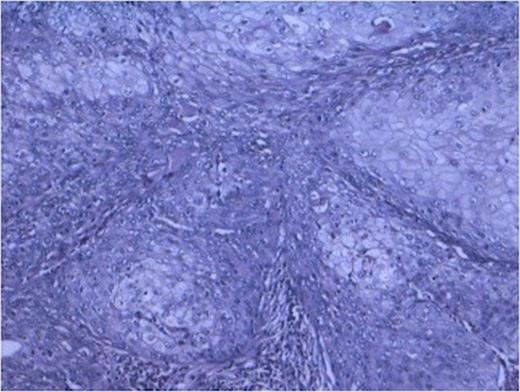

Histopathology from solid portions in pelvis region showed features of moderately differentiated squamous cell carcinoma (Fig 3). The tumor was not involving retroperitoneal soft tissue including renal vessels, Gerota’s fascia and lymph nodes.